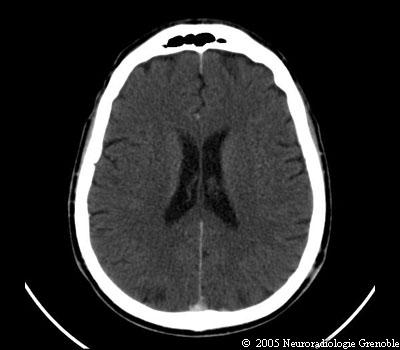

Radioanatomie TDM de l'encéphale

TDM cérébrale sans injection